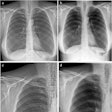

Dark-field chest x-ray images compared to conventional x-rays